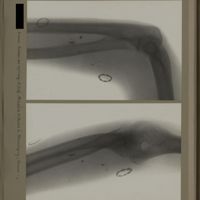

0134 - Page 22 - [Radiographies du coude et du tiers supérieur de l'avant-bras]0134 - Page 22 - [Radiographies du coude et du tiers supérieur de l'avant-bras]

0139 - Page 27 - [Radiographies du coude]0139 - Page 27 - [Radiographies du coude]

0144 - Page 32 - [Radiographies du coude]0144 - Page 32 - [Radiographies du coude]

0153 - Page 41 - [Radiographies du coude]0153 - Page 41 - [Radiographies du coude]